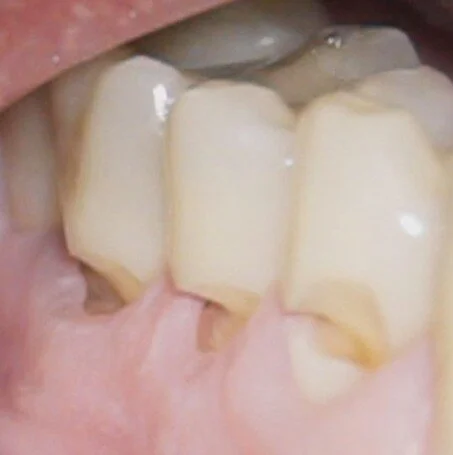

Abfractions

Abfractions are lesions in the sides of teeth near the roots. They are not cavities, but rather areas of the root that are mechanically or chemically worn out.